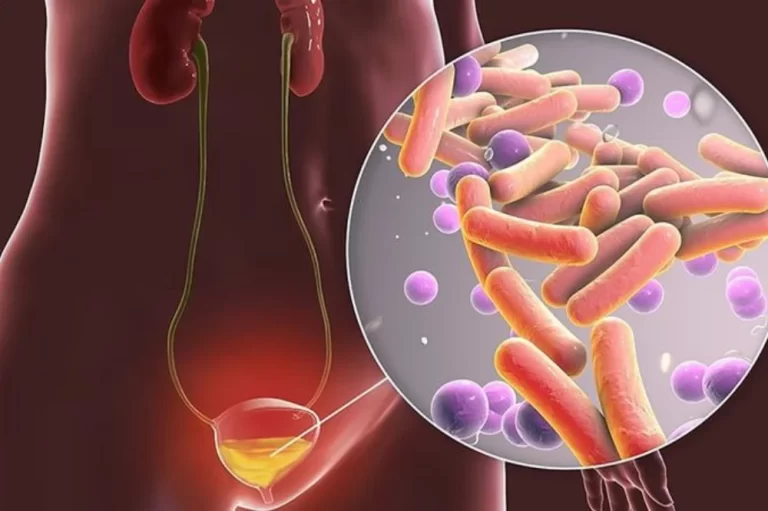

Nguyên nhân gây đa ối

Trong nhiều trường hợp: không rõ nguyên nhân

Tuy nhiên, có một số yếu tố liên quan:

1. Tiểu đường thai kỳ

- Là nguyên nhân phổ biến nhất

- Làm tăng lượng nước ối

2. Thai nhi nuốt ối kém

Do:

- Bất thường tiêu hóa

- Bất thường thần kinh

3. Mang đa thai

- Song thai dễ gặp đa ối hơn

4. Bất đồng nhóm máu

👉 Tuy nhiên:

Đa số trường hợp đa ối nhẹ vẫn không tìm được nguyên nhân rõ ràng